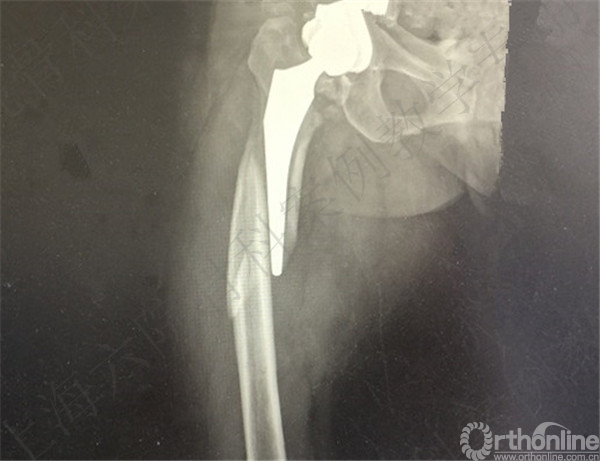

患者2周后自行下地摔倒至右髋假体周围骨折,假体松动,择期行长柄假体置换术+假体周围骨折切开复位内固定术。

术后X线摄片示:假体在位,骨折对位对线可。